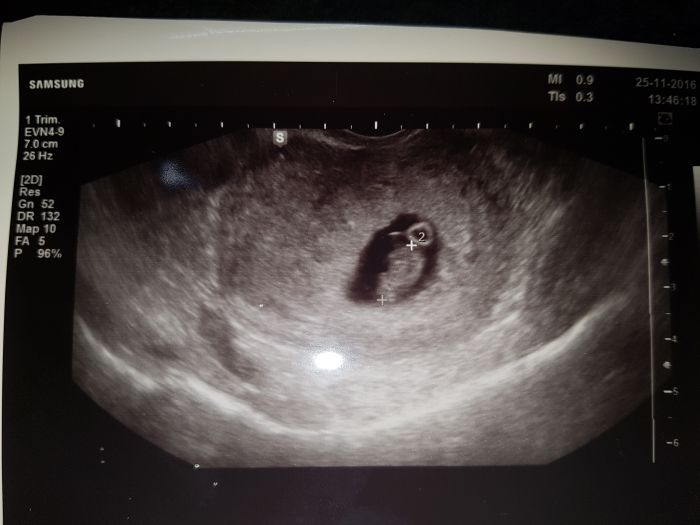

Tak ja jsem byla vcera u dr. Srdícko nam krasne bilo. Tak jsem stastna. A prdolka ma 1 a pul cm.

Dostala jsem i tehotenskou prukazku a mam se objednat na tu genetiku screening co se dela ve 12 tydnu. Pry jsou tam taky s temi terminy na stiru tak se objednat uz ted. Bude to stat pry 1400,- neco pry doplaci pojistovna.

A jeste prikladam fotecku.